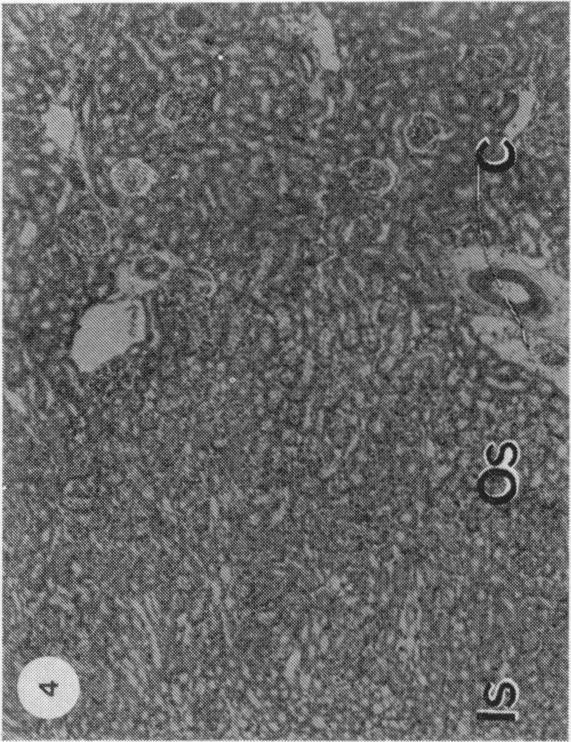

In JCLR and Wistar-Porton rats renal concentrations of Cd2+ were maximal (21-22 micrograms Cd2+/g wet wt tissue) at 1 and 4 h respectively after the administration of CdCl2 (10 micromol, 1-12 mg Cd2+/kg body wt) together with L-cysteine (5 mmol/kg body wt). Synthesis of metallothionein in the kidney in response to the uptake of Cd2+, which occurred between 2 and 7 h after treatment in the Wistar-Porton rat, affected the distribution of Cd2+ between proteins of the renal soluble fraction, but not between the particulate components and, at both times, about 40% of the total Cd2+ was associated with the heterogeneous nuclei + cell debris fraction. Autoradiographic studies with 109CdCl2 revealed that Cd2+, accumulated by the kidney under these conditions, was not uniformly distributed throughout the renal cortex, but was concentrated unevenly in proximal tubules in the outer stripe of the outer zone of the medulla. Pathological changes, which were correlated with the concentrations of accumulated Cd2+ and were limited to the S3 segments of the proximal tubules, were apparent by light microscopy at 4 h after the administration of Cd2+ + cysteine and progressed with time. Thus by 7 h the lesion had extended to include almost the whole of the outer stripe of the outer zone of the medulla and, by 24 h the cells of the affected epithelia showed extensive necrosis and karyorrhexis. At this, as at earlier times, the cortex appeared to be undamaged. Neither these nor other morphological changes were observed in the kidneys of animals that had been dosed with either Cd2+, or L-cysteine alone. Within 60 min of the administration of Cd2+ + cysteine an increase in the number of endocytotic vesicles in the apical cytoplasm of the proximal tubular epithelium was observed by electron microscopy. Subsequent cytoplasmic vesiculation, which was conspicuous at 2 h, was extensive and widespread in both the apical and basal regions of the cytoplasm at 4 h. In some cells at this time the nuclei were irregular in shape; the mitochondria were swollen and their cristae were disorganized. As, after the administration of either Cd2+ or cadmium-metallothionein, damage is known to occur in the S1 and S2 segments of proximal tubules throughout the cortex, the Cd2+ + cysteine combination does not provide an exact model which reproduces in a short time the effects of long-term, low level exposure to Cd2+. Nevertheless it is suggested that the toxic mechanisms are the same after either treatment with Cd2+ + cysteine or continual exposure to Cd2+, but are limited to different segments of the proximal tubules. Possible mechanisms of toxicity are discussed.

在JCLR大鼠和Wistar-Porton大鼠中,在给予氯化镉(10微摩尔,1-12毫克镉离子/千克体重)和L-半胱氨酸(5毫摩尔/千克体重)后,肾脏中镉离子的浓度分别在1小时和4小时达到最大值(21-22微克镉离子/克湿重组织)。在Wistar-Porton大鼠中,处理后2至7小时内,肾脏中因摄取镉离子而合成的金属硫蛋白影响了镉离子在肾脏可溶性部分蛋白质之间的分布,但不影响颗粒成分之间的分布,并且在这两个时间点,总镉离子的约40%与异质核+细胞碎片部分相关。用109氯化镉进行的放射自显影研究表明,在这些条件下肾脏积累的镉离子并非均匀分布于整个肾皮质,而是不均匀地集中在髓质外带外层的近端小管中。与积累的镉离子浓度相关且局限于近端小管S3段的病理变化,在给予镉离子+半胱氨酸后4小时通过光学显微镜可见,并随时间进展。因此,到7小时时,病变已扩展至几乎包括髓质外带外层的全部,到24小时时,受影响上皮细胞出现广泛坏死和核碎裂。此时,如同早期一样,皮质似乎未受损伤。单独给予镉离子或L-半胱氨酸的动物肾脏中未观察到这些或其他形态学变化。在给予镉离子+半胱氨酸后60分钟内,通过电子显微镜观察到近端小管上皮细胞顶端细胞质内吞小泡数量增加。随后的细胞质空泡化在2小时时明显,在4小时时在细胞质的顶端和基部区域广泛且普遍存在。此时在一些细胞中,细胞核形状不规则;线粒体肿胀且嵴紊乱。由于已知在给予镉离子或镉-金属硫蛋白后,整个皮质近端小管的S1和S2段会发生损伤,镉离子+半胱氨酸组合并不能提供一个能在短时间内重现长期低水平接触镉离子影响的精确模型。然而,有人认为,用镉离子+半胱氨酸处理或持续接触镉离子后的毒性机制相同,但局限于近端小管的不同段。文中讨论了可能的毒性机制。